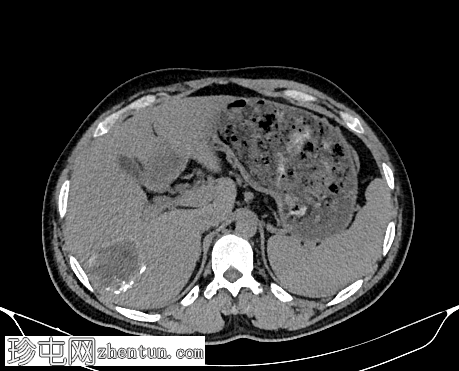

轴位增强扫描(门静脉期)

肝脏VII段可见一边界清晰的囊性病变,内部有分隔,囊壁可见钙化。

右肾中央部分(肾门)可见一囊性病变,中心可见基质,周围可见子囊。该病变与肾盂肾盏无交通。病变周围可见两处高密度影,位于上、中肾盏,无法区分是结石还是病变壁钙化。另可见上极肾盏中度扩张。